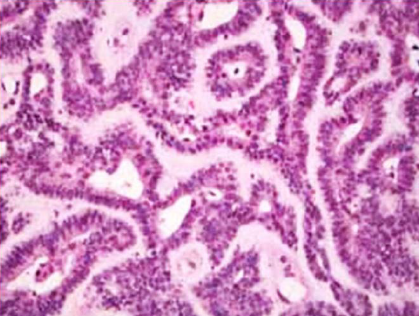

Polymorphous (Low-grade)adenocarcinoma (PLGA) Palate,老人

• 好發: minor salivary g., Palate(65%)

• 多型態,邊界清楚

• 見神經侵犯

• CD43(week+), CD117(week+), GFAP(-)

• 預後好

• 微鼓起,中間有ulcer

• Indian-file